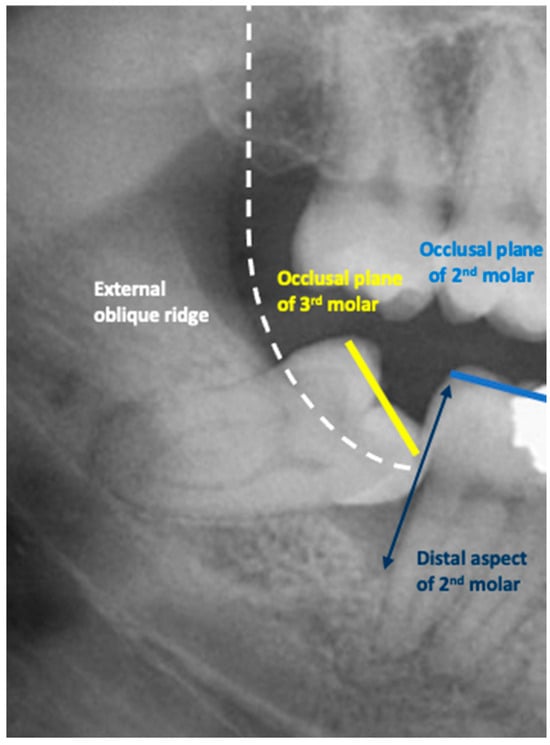

In this study, partial emergence or partial eruption of the mandibular third molar was determined by assessing the position of the third molar in relation to that of the adjacent mandibular second molar. Figure 1 illustrates a partially erupted mandibular and impacted third molar as seen on a bitewing radiograph, while Figure 2 illustrates a panoramic tomograph of a mandibular third molar that was deemed to be partially erupted. We judged the partial eruption of the third molar from the cusp levels; the third molars were deemed to be partially emerged when one of the cusps was positioned above the occlusal plane level or above the external oblique ridge. In cases in which these anatomical landmarks were not visible on the radiograph, the cementoenamel junction (CEJ) of the adjacent second molar in relation to the position of the marginal ridge of the adjacent mandibular third molar was used to obtain information on the depth of the third molar and was used to judge its eruption status [12]. This assessment method is a modification of the original Pell and Gregory classification [13]. Classes IIIA, IB, IIB and IIIB of the original Pell and Gregory categorization were included, thus excluding fully erupted potentially functional and fully impacted third molars. This classification (Figure 3) was applied to all third molar impaction types such as mesial, horizontal, distal, vertical and transverse.

Figure 3. Diagram of the classification used to analyze the ratio of second to third molars to determine partial eruption (modified Pell and Gregory classification) [13].